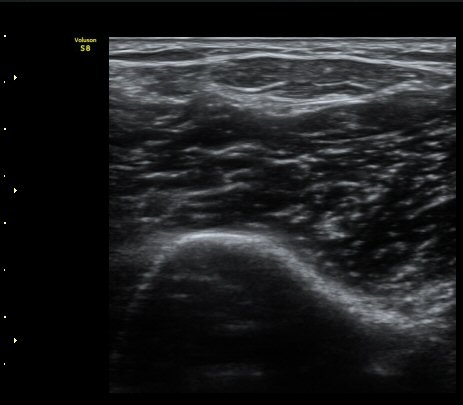

ÆÈ²ÞÄ¡ ¾Õ Ⱦ´Ü¸é°Ë»ç¿¡¼­ À̵ιڱÙÀÌ ÈûÁÙ·Î ÀÌÇàµÇ´Â °ÍÀÌ °üÂûµÈ´Ù(±×¸² 1, 2).

ŽÃËÀÚ¸¦ Á¶±Ý ¸»´ÜÀ¸·Î À̵¿ÇÏ´Ï À̵ιڱ٠ÈûÁÙÀÌ ¶Ñ·ÈÇÏ°Ô °üÂûµÇ°í ÇÔÁÙ ÁÖÀ§¿¡

¼ö¾×Àú·ù°¡  º¸ÀδÙ(±×¸² 3, 4, 5, 6)